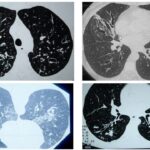

Hoje quero fazer um vídeo bem completo, contando minha trajetória e também explicando para vocês sobre essa condição. Para começar, quero explicar que bronquiectasia é uma doença irreversível, ou seja, não tem cura. É uma dilatação dos brônquios e bronquíolos, que são lugares onde passa o nosso ar. Quando isso acontece, aquela parte que está afetada não funciona mais.

Foi a primeira vez que fiz uma tomografia, há dez anos atrás. Fiquei apreensiva para saber o resultado. Ela disse que o resultado mostrava uma cicatriz, e que era por isso que apareceu aquela bolinha na tomografia. Ela falou que eu tinha bronquiectasia no lobo médio e superior esquerdo. Ela me liberou e passou tratamento, mas não fiz fisioterapia na época. Eu não sabia o que era bronquiectasia e ela não explicou direito. Achava que era só bronquite ou uma infecção.

Agora estou usando a bombinha três vezes por dia e faço exames regularmente. Ela me acompanha sempre e me ajuda quando estou me sentindo mal. Estou sendo bem amparada. Se eu precisar trocar de médica, tenho que fazer uma receita para nova tomografia, pois vimos que meu lobo médio estava todo comprometido. Ele estava até diminuído, pois tinha muita bronquiectasia. Por causa das infecções recorrentes, talvez faça outra cirurgia, mas ainda não sei ao certo. Tudo está nas mãos de Deus.